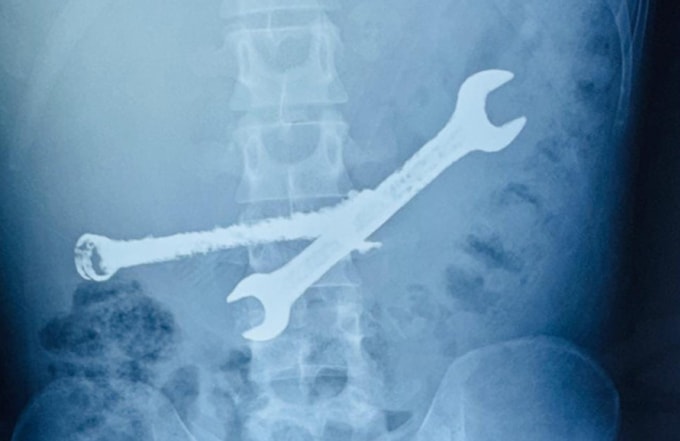

Các bác sĩ tại thành phố Jaipur vừa phẫu thuật khẩn cấp, lấy ra hai chiếc cờ lê sắt và 7 bàn chải đánh răng găm chặt trong dạ dày nam bệnh nhân 26 tuổi.

Bác sĩ Tanmay Pareek, chuyên gia tiêu hóa trực tiếp điều trị, cho biết kết quả chẩn đoán hình ảnh ban đầu khiến cả êkíp kinh ngạc. Dạ dày người bệnh chứa đầy các vật thể cứng với hình thù dị thường, trông không khác gì một thùng chứa phế liệu.

Sau hơn hai giờ căng thẳng, kíp mổ lần lượt lấy ra hai chiếc cờ lê bằng sắt và 7 bàn chải đánh răng còn nguyên vẹn. Bác sĩ Pareek nhận định bệnh nhân mắc chứng rối loạn tâm thần nhẹ, dẫn đến hành vi nuốt các vật thể không phải thực phẩm (hội chứng Pica). Thói quen nguy hiểm này xuất hiện khoảng một tháng trước khi nhập viện, các dị vật tích tụ dần gây tổn thương nghiêm trọng cơ quan tiêu hóa.